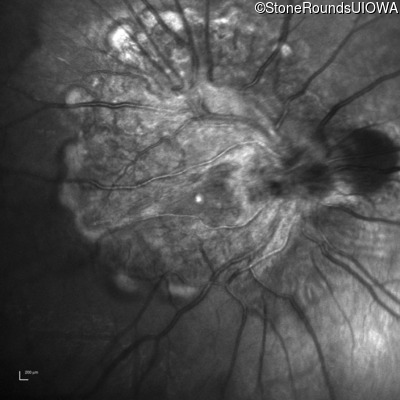

Infrared Fundus Photograph - Right - 20/2000

Exemplar